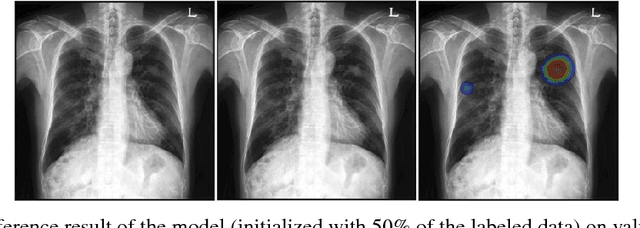

Abstract:Machine learning applications in medical imaging are frequently limited by the lack of quality labeled data. In this paper, we explore the self training method, a form of semi-supervised learning, to address the labeling burden. By integrating reinforcement learning, we were able to expand the application of self training to complex segmentation networks without any further human annotation. The proposed approach, reinforced self training (ReST), fine tunes a semantic segmentation networks by introducing a policy network that learns to generate pseudolabels. We incorporate an expert demonstration network, based on inverse reinforcement learning, to enhance clinical validity and convergence of the policy network. The model was tested on a pulmonary nodule segmentation task in chest X-rays and achieved the performance of a standard U-Net while using only 50% of the labeled data, by exploiting unlabeled data. When the same number of labeled data was used, a moderate to significant cross validation accuracy improvement was achieved depending on the absolute number of labels used.